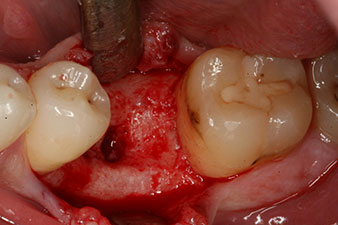

Figura 2: Seis semanas después, se observó un alvéolo que solo estaba osificado de forma incompleta en el área de la raíz mesial.

No obstante, seis semanas después de la extracción, tras la disección del colgajo mucoperióstico, se observó una osificación incompleta en el área del antiguo alvéolo mesial.